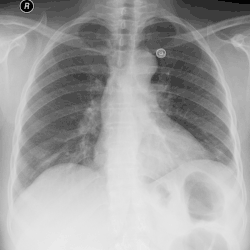

Bei der körperlichen Untersuchung sind ein abgeschwächtes Atemgeräusch bei der Auskultation und ein gedämpfter (hyposonorer) Klopfschall bei der Perkussion über dem Pleuraempyem typisch aber unspezifisch. Für die Diagnose von Pleuraempyemen reicht meist eine konventionelle Röntgenaufnahme des Brustkorbs. Pleuraempyeme sind hier durch eine deutliche Transparenzabnahme gekennzeichnet. Die Eiteransammlung zeigt sich im Röntgenbild in Form einer Spiegelbildung. Bei unklaren Befunden kann eine Computertomographie des Brustkorbs angefertigt werden.